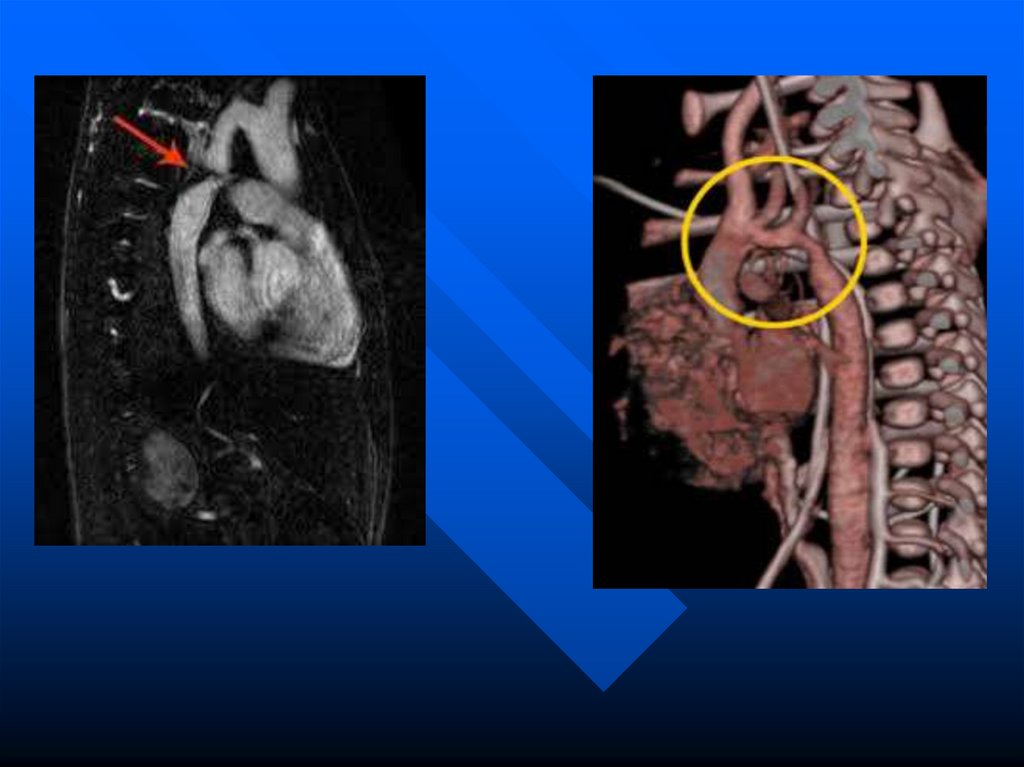

аномалии сердечно-сосудистой

системы возникают с 3 по 8

неделю развития плода.

8.